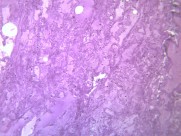

肺水肿(pulmonaryedema)是肺脏内血管与组织之间液体交换功能紊乱所致的肺含水量增加本病可严重影响呼吸功能,是临床上较常见的急性呼吸衰竭的病因。主要临床表现为极度呼吸困难,端坐呼吸,紫绀,大汗淋漓,阵发性咳嗽伴大量白色或粉红色泡沫痰,双肺布满对称性湿啰音,X线胸片可见两肺蝶形片状模糊阴影,晚期可出现休克甚至死亡。动脉血气分析早期可有低O2、低CO2分压、严重缺O2、CO2 潴留及混合性酸中毒。